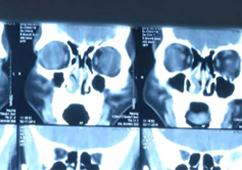

检查:鼻内窥镜检查、鼻部CT

检查:鼻内窥镜检查、鼻部CT

检查:鼻内窥镜检查、鼻部CT